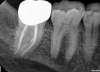

(4.) Radiographs of teeth treated with prefabricated and custom cast posts, respectively.

Figure 4